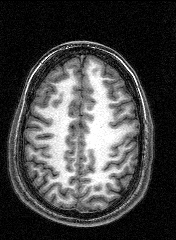

The last session involved several MRI and fMRI scans while completing tasks in the noisy environment of the scanner. Thanks to a friend who worked at the Institute, I was able to secure a copy of the raw data and an application to turn it into images, some of which are displayed here.

The images to the right are virtual 'slices', taken horizontally, starting from the top and working down. Cerebrospinal fluid is dark, the white matter appears light.

Medical images such as these are easy to come by on the internet, but having images of your own brain brings a humbling perspective.